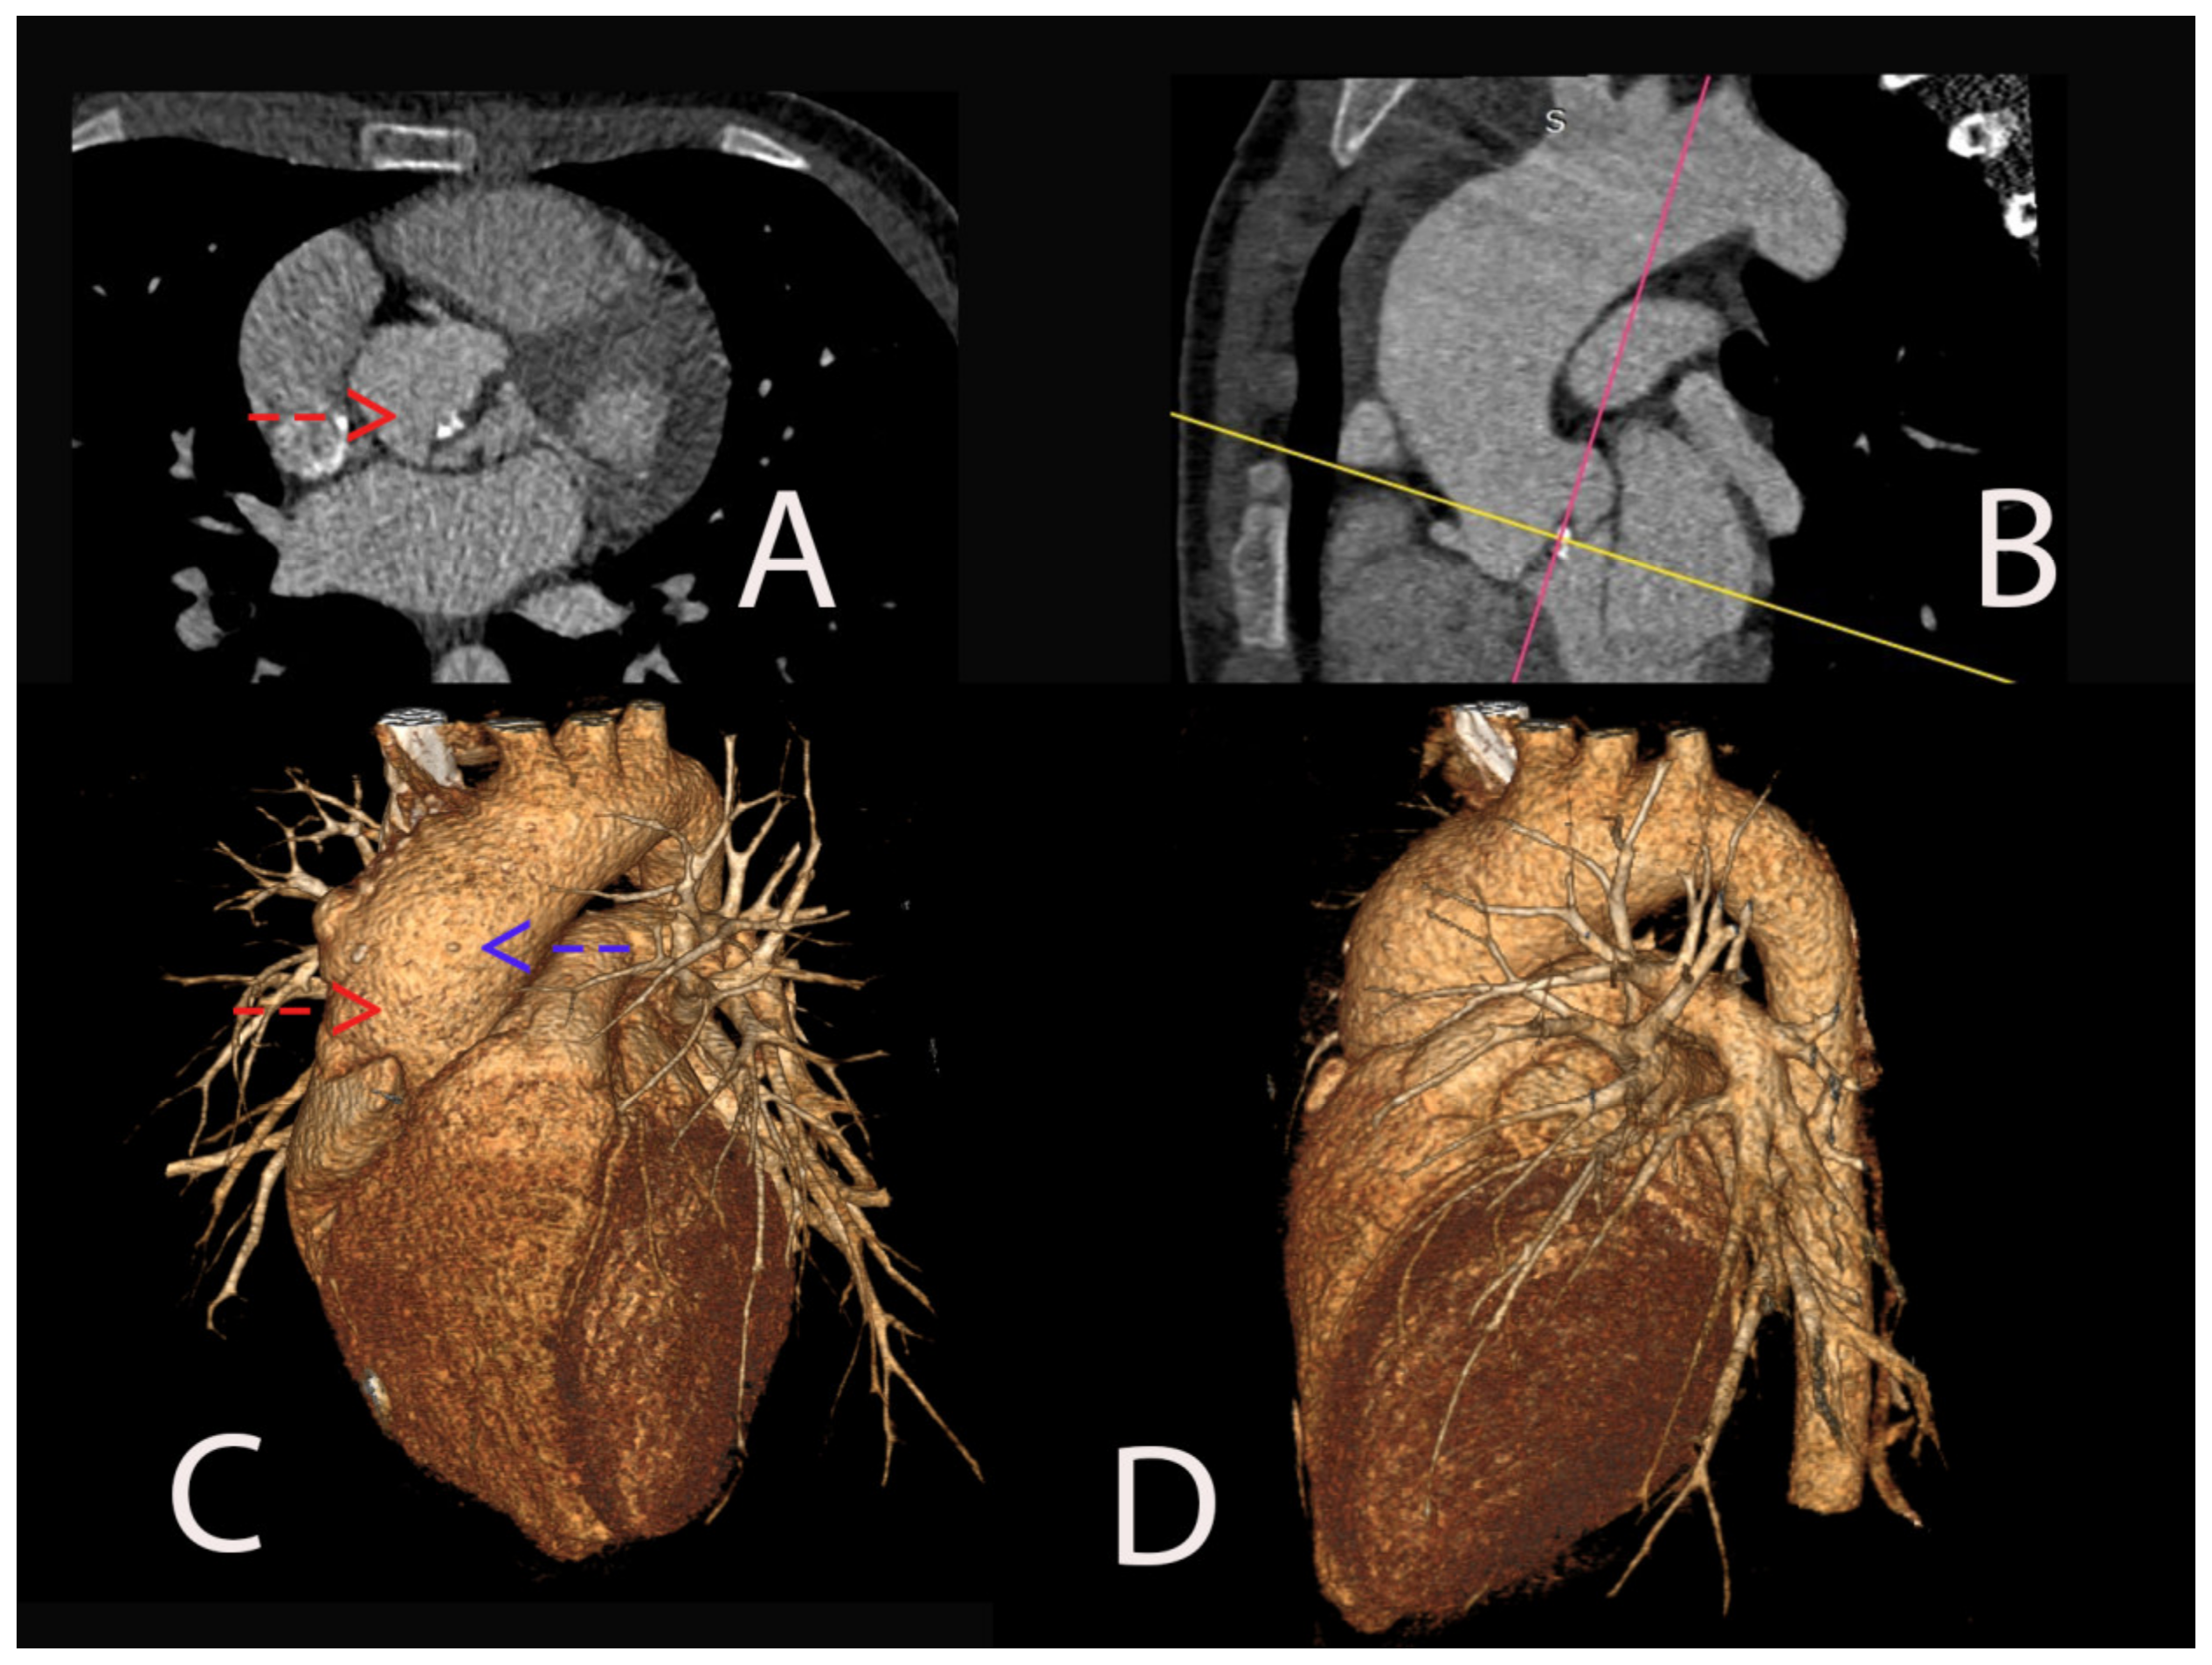

2. Case Presentation